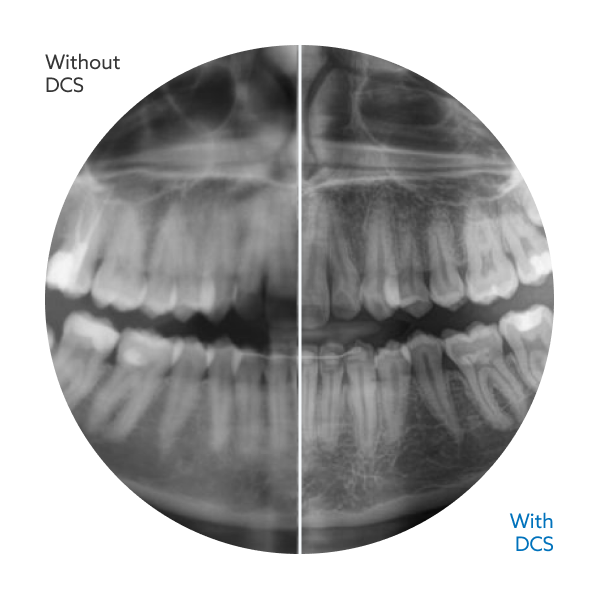

The Direct Conversion Sensor (DCS) sets a new standard for panoramic imaging by converting X-rays directly into electrical signals, eliminating the signal loss associated with traditional light conversion systems. This advanced technology delivers sharper, more detailed images while maintaining an impressively low radiation dose, giving you the clarity and confidence needed for accurate diagnostics.